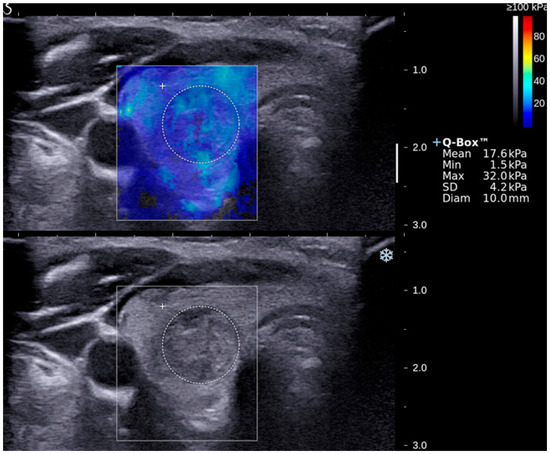

| SWE Indices | Median ± 1 Standard Error | p-Value (95% Confidence Interval) | |

| Benign | Malignant | ||

| Emax | 50.3 ± 3.1 | 85.2 ± 8.1 | <0.05 (50.9–63.5; 73.0–106.1) |

| Emean | 20.2 ± 1.0 | 26.6 ± 2.5 | <0.05 (19.5–23.5; 23.5–33.9) |

| Emin | 3.9 ± 0.6 | 3.8 ± 1.2 | >0.05 (4.2–6.4; 3.7–8.8) |

| Emax (67.3 kPa) | 70.4 | 70.2 | 43.2 | 88.1 | 70.3 | 0.785 |

| Emean (23.1 kPa) | 74.1 | 66.7 | 41.7 | 88.9 | 68.5 | 0.710 |

| GSU + Emax (67.3 kPa) | 70.4 | 83.3 | 57.6 | 89.7 | 80.2 | 0.769 |

| GSU + Emean (23.1 kPa) | 74.1 | 79.8 | 54.1 | 90.5 | 78.4 | 0.775 |